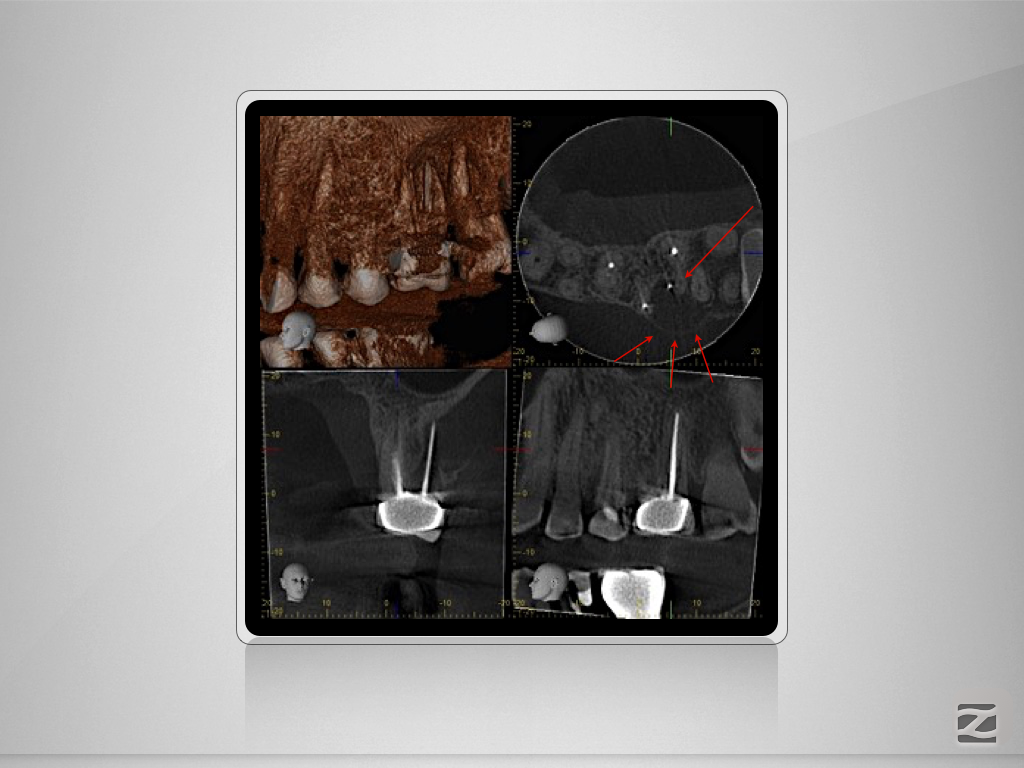

2526d-003

Enter Sandman